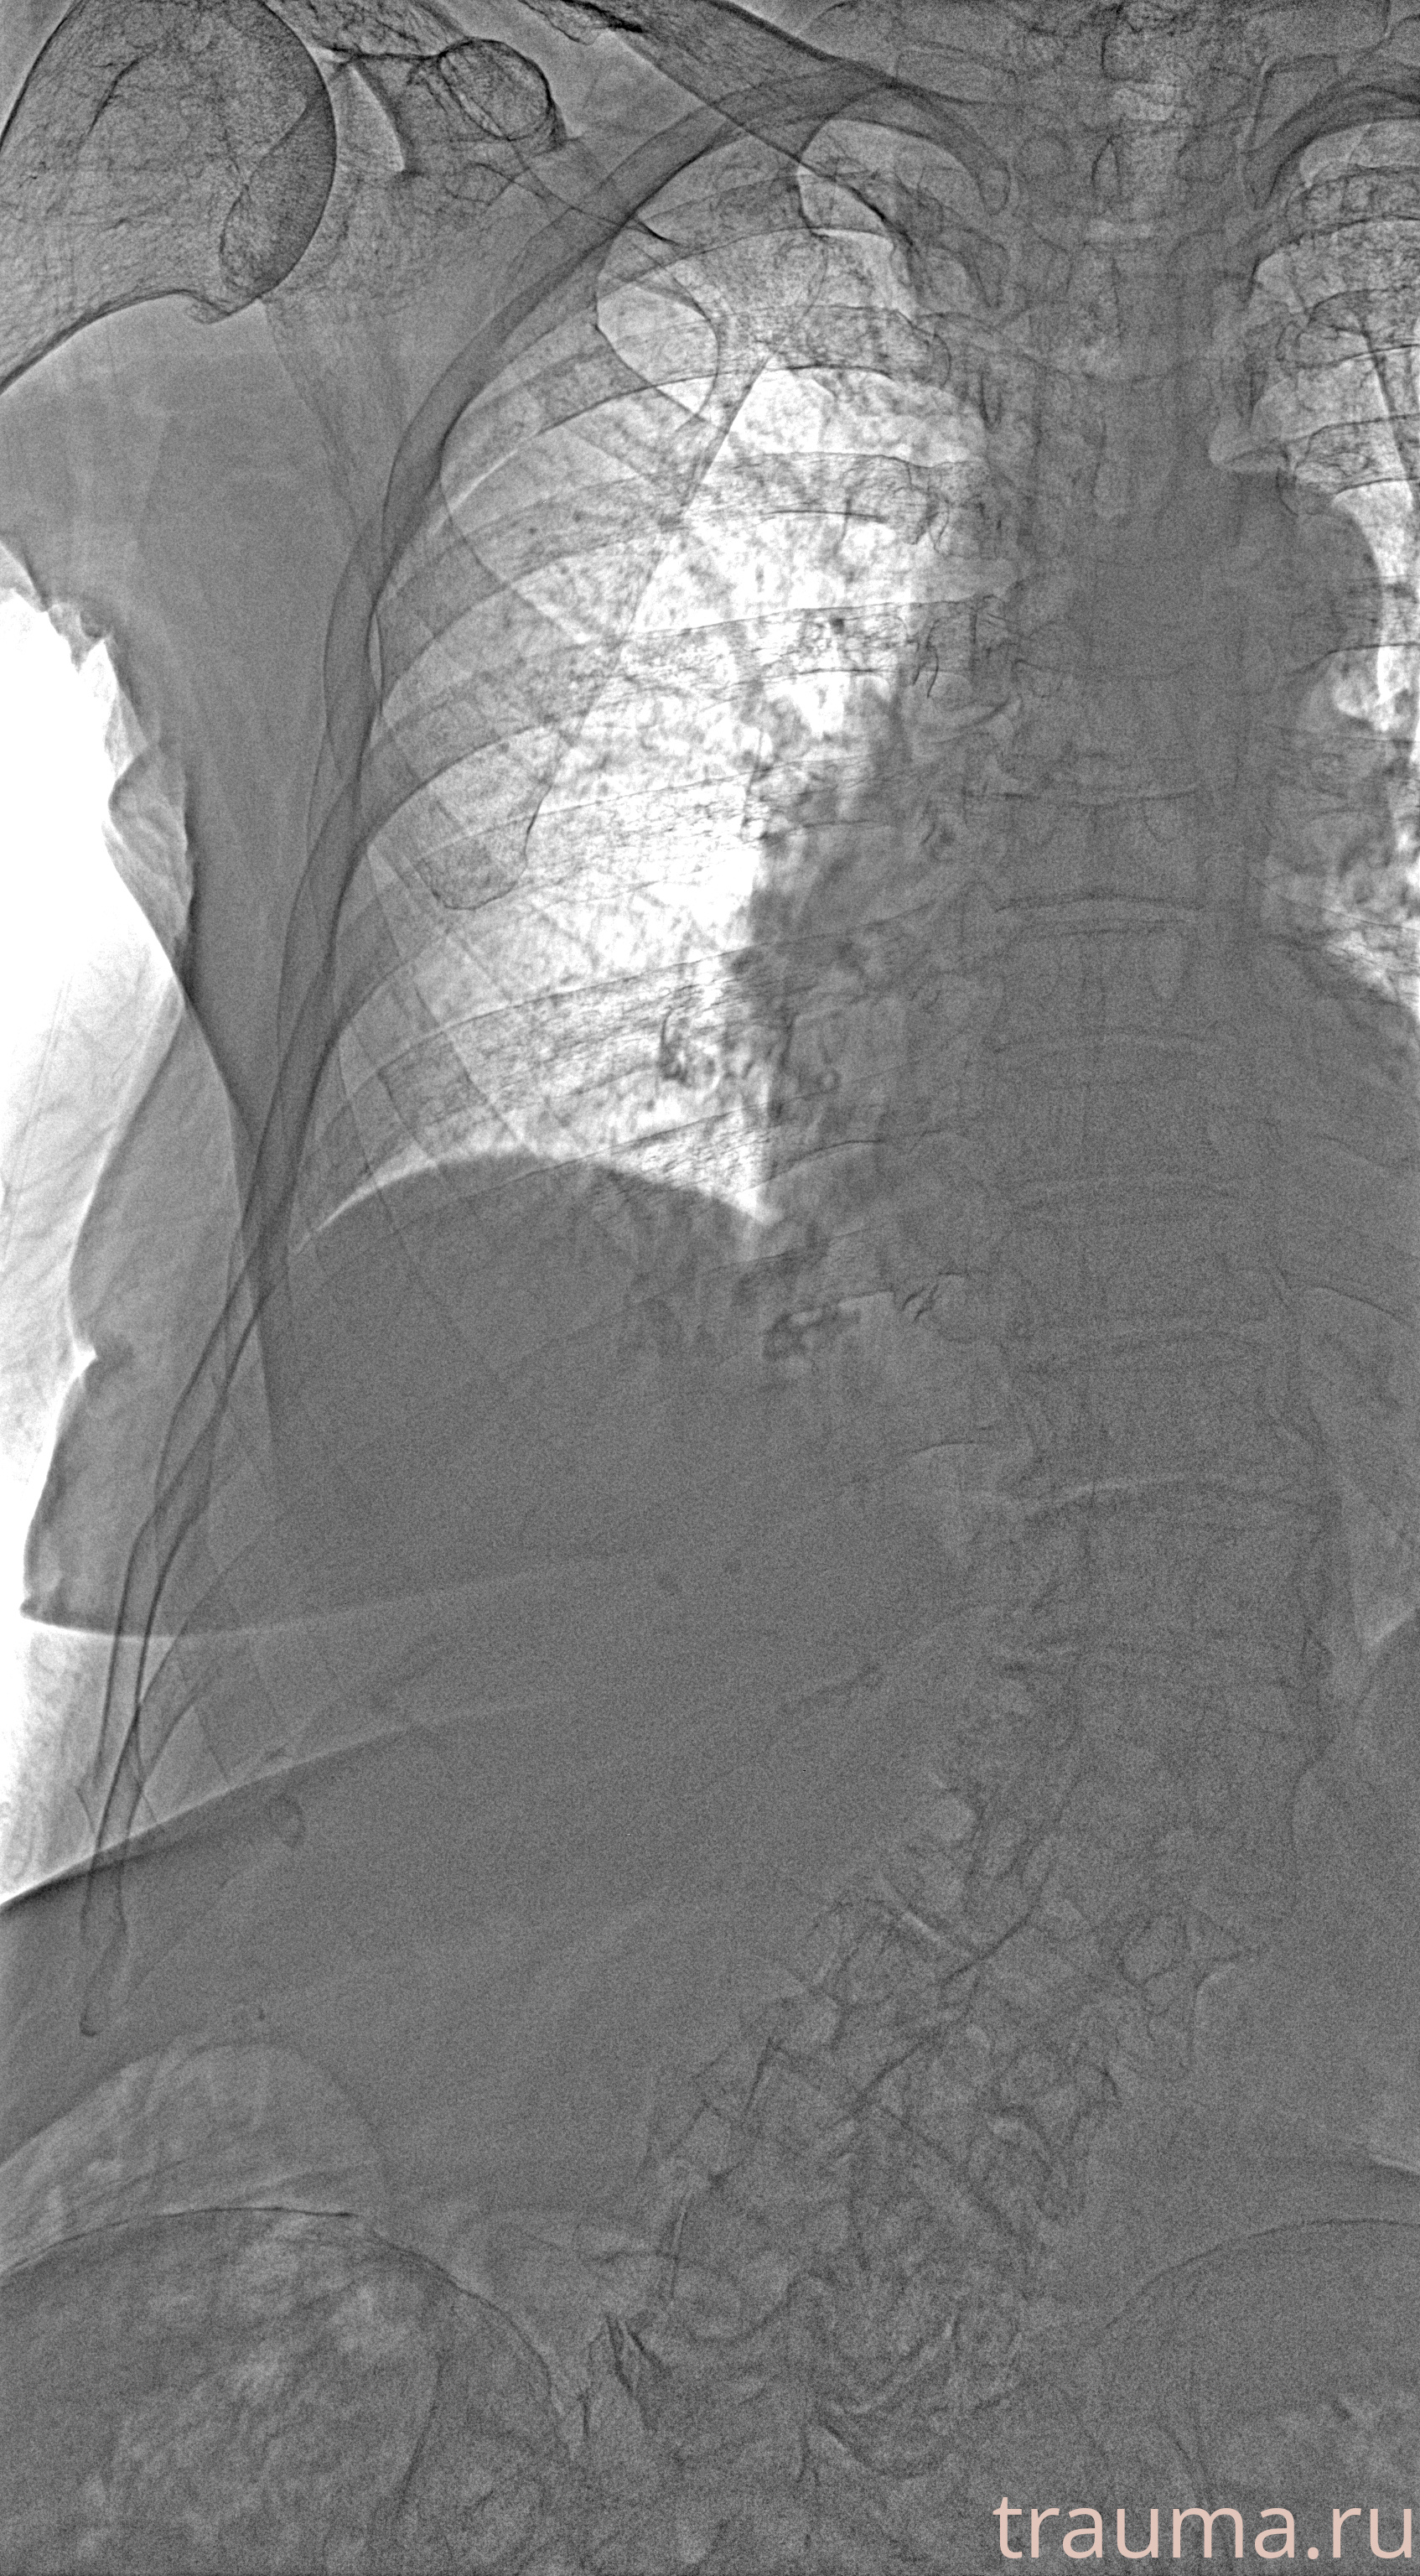

Рентген на дому: по вашему адресу приезжает врач-рентгенолог, травматолог-ортопед с мобильным рентгеновским аппаратом, проводит диагностику травмы или заболевания, делает необходимые рентгенограммы, дает рекомендации по дальнейшему лечению. Получить качественные снимки в домашних условиях возможно благодаря уникальной методике, разработанной МосРентген Центром для института  Склифосовского